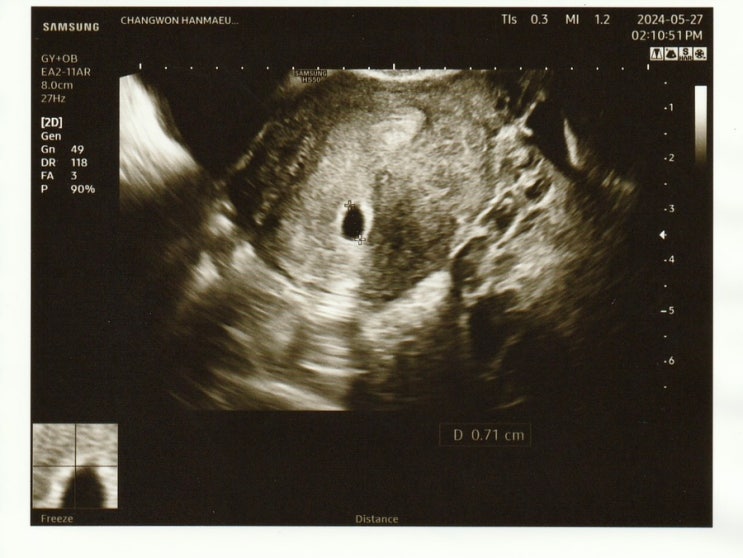

임신 4w5d / 아기집 확인 / 임산부 등록 / 창원한마음병원

다시 my baby 카테고리에 글을 쓰게 되다니..✨ 2024. 05. 27 (월) 오늘로써 마지막일 것 같은 임테기 ! 이...